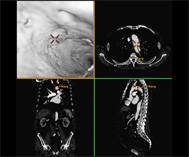

仮想血管内視鏡

CT画像を用いた3次元画像は今でこそ多くの施設で活用されるようになりましたが、その開発に当放射線科は深く関ってきました。現在では、大動脈瘤や大動脈解離などの大血管疾患や閉塞性動脈硬化症などの末梢血管疾患に加え心臓の冠動脈の3次元画像も提供できるようになり、これまで血管造影でしか得られなかった情報をおよそ10分程度の外来検査で正確に知ることができるようになりました。また、早期脳梗塞の診断において注目されているCT perfusion(CT灌流画像)も海外の大学と共同で開発し国内外での普及に努めてきました。これらの成果は欧州放射線学会から金賞ならびに銀賞を授与され、また日本医学放射線学会でも金賞を受賞し、広く国内外で認められています。